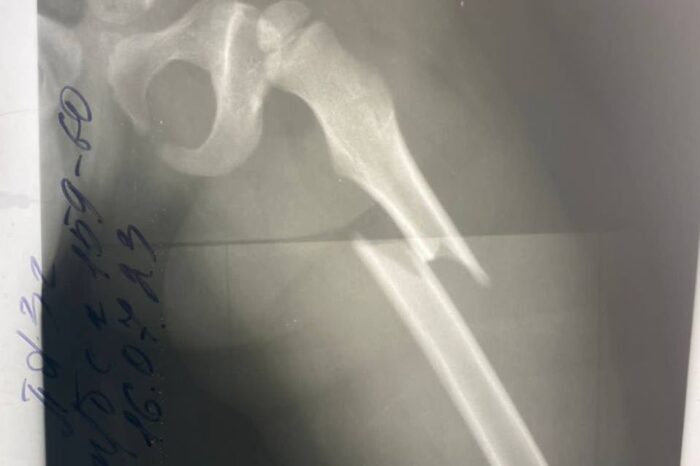

У маленькой девочки диагностировали закрытый перелом левого бедра со смещением отломков.

У маленькой девочки диагностировали закрытый перелом левого бедра со смещением отломков. Врачи смогли избежать лечения со скелетным вытяжением.

Ребенок поступил в детскую областную больницу в конце июля. Девочка упала с качелей и получила сложный перелом бедра — серьезная патология для дальнейшего роста и развития ребенка.

Ребенка успешно прооперировали и установили металлическую конструкцию. На пятые сутки малышку уже выписали. Через несколько недель девочке разрешат нагрузку на ногу, а через год удалят металлоконструкцию из бедра.

Медики подчеркивают, что раньше такие случаи у детей лечились на скелетном вытяжении в течение полутора месяцев. Сегодня новые методики позволяют даже не накладывать гипс, так как перелом срастается быстрее.